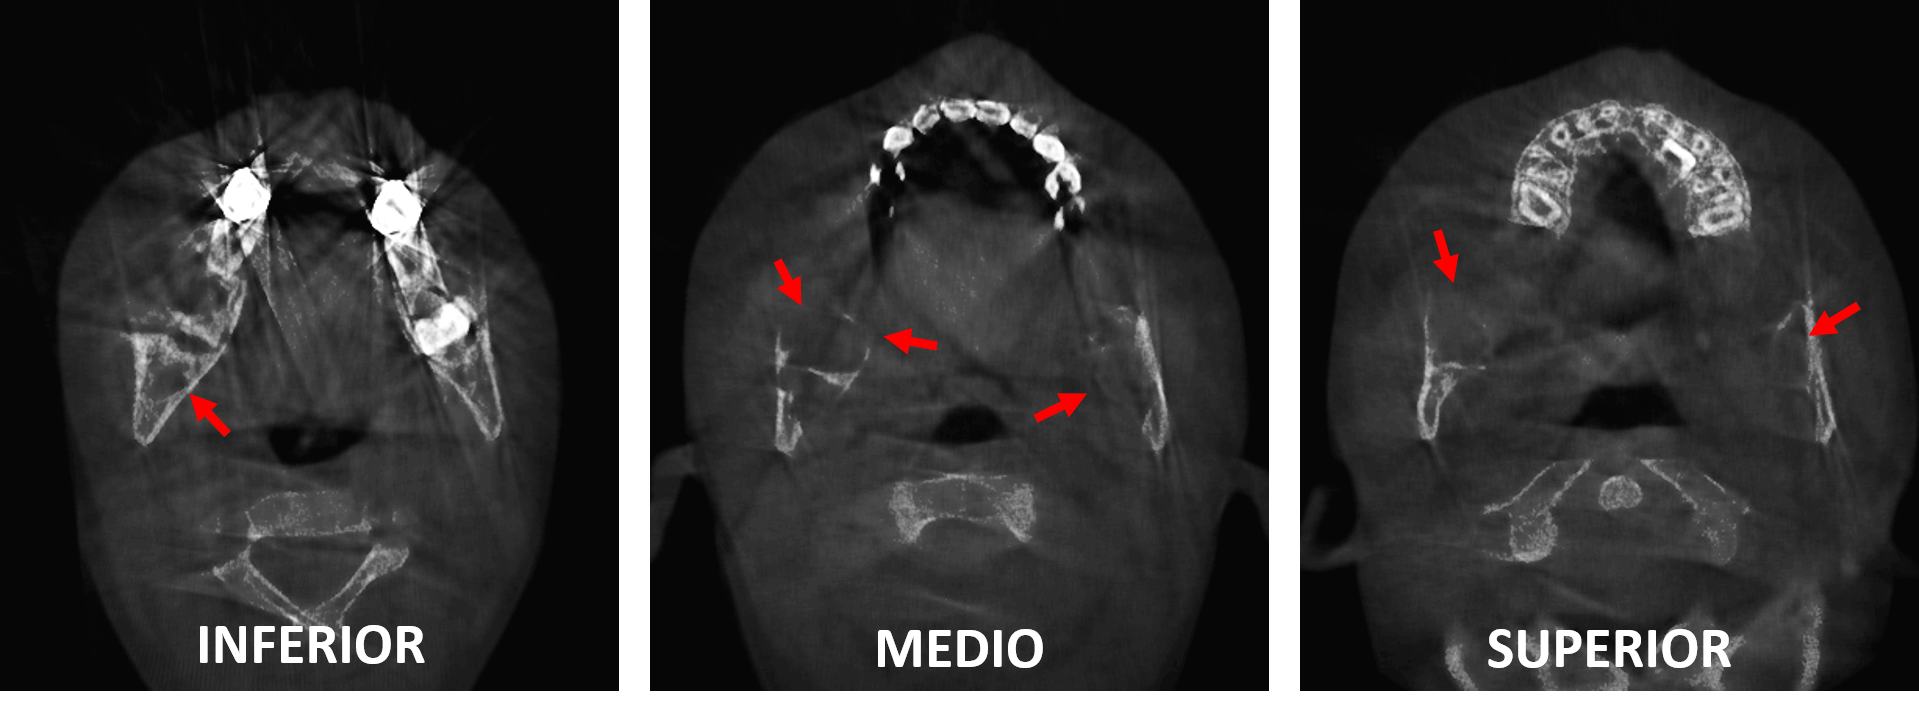

Fig.3

En el corte sagital del lado derecho (Fig.3) se observa la lesión osteolítica condiciona, la leve expansión, adelgazamiento y probable erosión de la cortical ósea del borde anterior de la rama ascendente (flechas rojas).

Fig.4

En el corte sagital del lado izquierdo (Fig.4) se observa también los mismos signos tomográficos del lado derecho, con la diferencia que de este lado la lesión es más pequeña, sin embargo, se encuentra en relación con el germen dentario del órgano dentario 47.